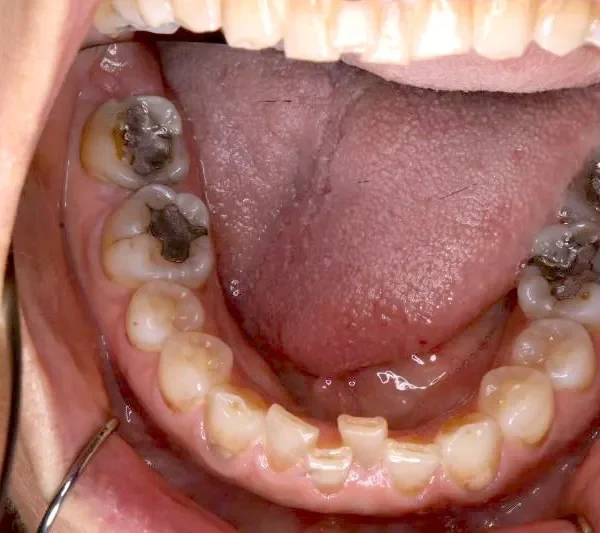

2.診断名あるいは主な症状 空隙歯列・先天性欠損歯

上の歯が2本足りないため上下のアーチが合わず、下の歯がガタガタになっています。

上下の幅をあわせ、噛み合わせから調整していきます。